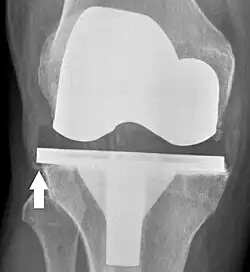

Componentes y zonas

Las zonas estandarizadas alrededor de los componentes se utilizan para especificar, por ejemplo, signos de aflojamiento en el seguimiento radiográfico. Existen varios sistemas de clasificación para especificar tales zonas,[40][41] incluso por zonas SR (Sociedad de la Rodilla) publicadas en 2015.[39]

Zonas SR, vista anteroposterior (AP).[39]

Las zonas específicas de SR son las siguientes, con * lo que significa que la zona se puede especificar como "A" (anterior), "P" (posterior), "M" (medial) o "L" (lateral):[39]

- Componente tibial:

- Zona 1: Vista anterior sobre lateral, medial sobre proyección anteroposterior (AP).

- Zona 2: Posterior en proyección lateral, lateral en proyección AP.

- Zona 3: Región de fijación central de quilla/vástago/clavija*

- Zona 4: Extensión de tallo*

- Zona 5: Aspecto inferior de la quilla o el tallo